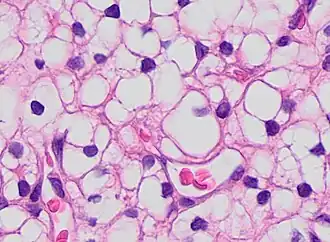

This can be done to slides processed by the chemical fixation or frozen section slides. To see the tissue under a microscope, the sections are stained with one or more pigments. The aim of staining is to reveal cellular components; counterstains are used to provide contrast.

The most commonly used stain in histology is a combination of hematoxylin and eosin (often abbreviated H&E). Hematoxylin is used to stain nuclei blue, while eosin stains the cytoplasm and the extracellular connective tissue matrix of most cells pink. There are hundreds of various other techniques which have been used to selectively stain cells. Other compounds used to color tissue sections include safranin, Oil Red O, congo red, silver salts and artificial dyes. Histochemistry refers to the science of using chemical reactions between laboratory chemicals and components within tissue. A commonly performed histochemical technique is the Perls' Prussian blue reaction, used to demonstrate iron deposits in diseases like Hemochromatosis.[2]